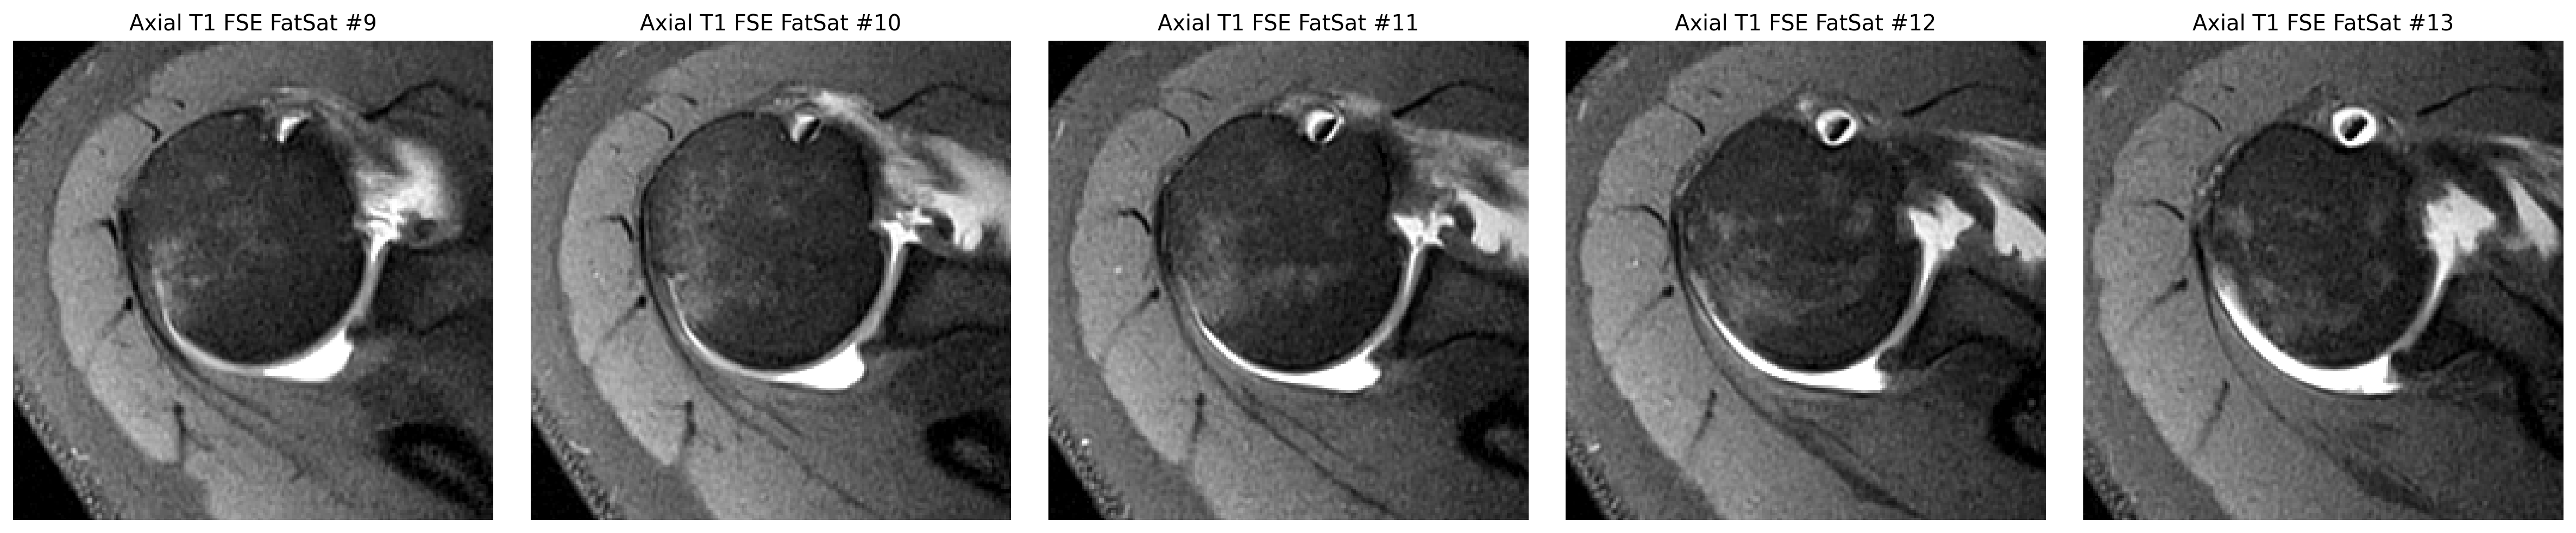

Whether there is a definite labral tear

The cuff finding was checked in coronal and sagittal views, while the labrum was reviewed on axial arthrogram slices.